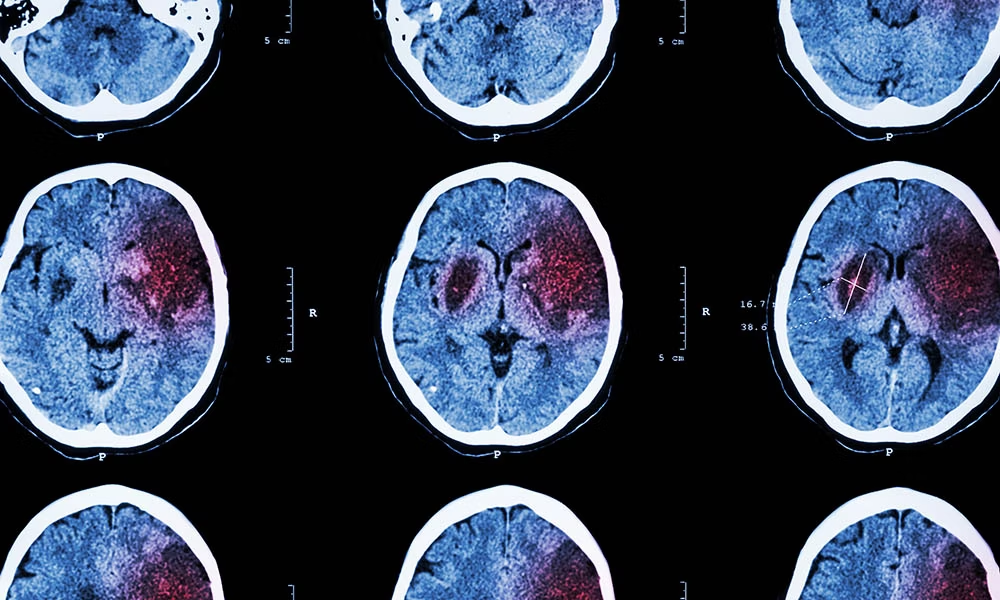

為了確保有針對(duì)性的治療,有必要確定患者是否患有血流量減少或腦出血。這通常通過(guò)成像技術(shù)來(lái)完成,例如大腦的計(jì)算機(jī)斷層掃描 (CT) 和/或磁共振成像 (MRI)。

中風(fēng)會(huì)破壞大腦的血液供應(yīng)(由于血流量減少或腦出血)。除臨床神經(jīng)學(xué)檢查外,還通過(guò)影像技術(shù)(CT、MRI)進(jìn)行診斷。